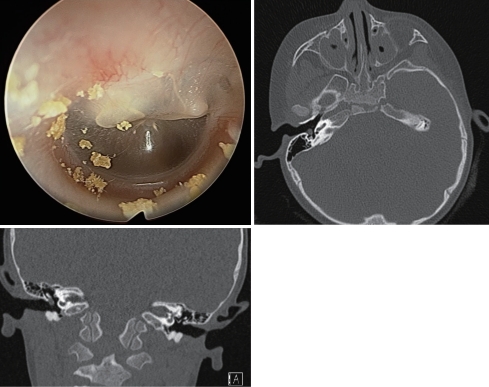

특이 과거력이 없는 2세 여아가 우측 고막의 흰색 종물 소견으로 내원하였다. 환아가 호소하는 특이 증상은 없었다. 다음은 외래에서 시행한 내시경 사진과 전산화단층촬영 사진이다. 이 질환에 대한 설명으로 맞지 않은 것을 고르시오.

① 선천성 진주종을 의심할 수 있다.

② 제시된 사진에서는 중고실 내에 국한된 병변임을 확인할 수 있다.